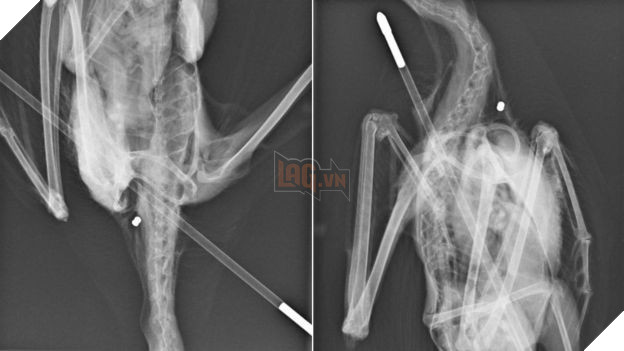

Do vết thương khá nghiêm trọng nên phòng khám của Hội RSPCA đã quyết định cho con hải âu chụp ảnh X quang. Nhìn kết quả, họ vô cùng bất ngờ khi phát hiện ra không chỉ có mũi tên, chú hải âu còn từng bị bắn súng hơi và viên đạn vẫn còn nằm trong cơ thể.

Cô Jo Blackburn, người trực tiếp bắt được con hải âu và đang làm việc tại tổ chức RSPCA, cho biết: "Thật tội nghiệp khi nhìn thấy chú hải âu bị tên đâm xuyên vào người. Càng buồn hơn khi có cả một viên đạn súng hơi bên trong cơ thể nó, chắc chắn là xuất hiện trước khi bị mũi tên xuyên qua vì trên thân chim không có thêm bất kì một vết thương hở nào khác, chứng tỏ vết thương cũ đã lành thì bị tấn công lần nữa".

Hình ảnh X quang cho thấy nó đã bị bắn không chỉ 1 lần!

Rất may mắn là đội ngũ bác sĩ đã tiến hành phẫu thuật loại bỏ các dị vật thành công cho chú chim. Mũi tên lấy ra có chiều dài tới 71 cm, phần lông đuôi có màu xanh lá và đen. Hiện tại, Hội RSPCA đang khẩn thiết kêu gọi mọi người tìm kiếm chủ nhân của mũi tên này.